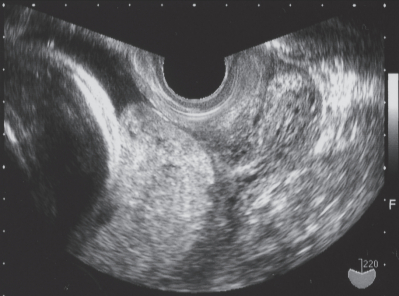

体温 36.5 ℃。 脈拍 84/分、整。血圧108/64 mmHg。腟鏡診で腟内に凝血塊の貯留を認め、子宮口から血液流出が持続している。計測できた出血量は約 250 mL である。腹部超音波検査で胎児推定体重2,230 g、羊水量は正常。胎児心拍数陣痛図で 10 分ごとの子宮収縮を認め、胎児心拍数波形に異常を認めない。経腟超音波像を別に示す。